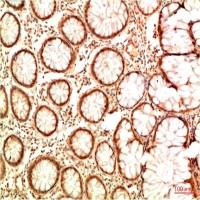

乙酰化抗体